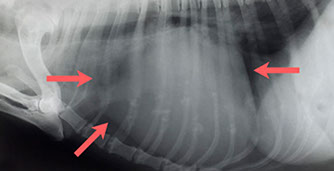

Mehrfachfrakturen nach Autounfall mit Lähmung der Hinterextremitäten bei einem Hund